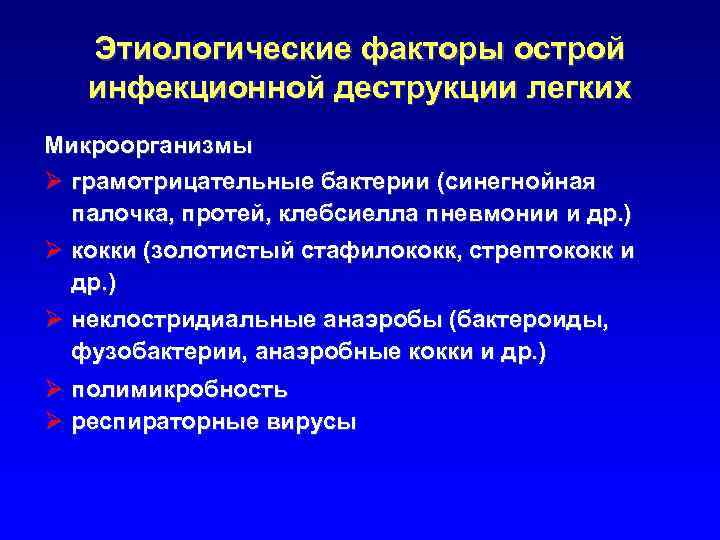

Этиологические факторы острой инфекционной деструкции легких Микроорганизмы Ø грамотрицательные бактерии (синегнойная палочка, протей, клебсиелла пневмонии и др. ) Ø кокки (золотистый стафилококк, стрептококк и др. ) Ø неклостридиальные анаэробы (бактероиды, фузобактерии, анаэробные кокки и др. ) Ø полимикробность Ø респираторные вирусы